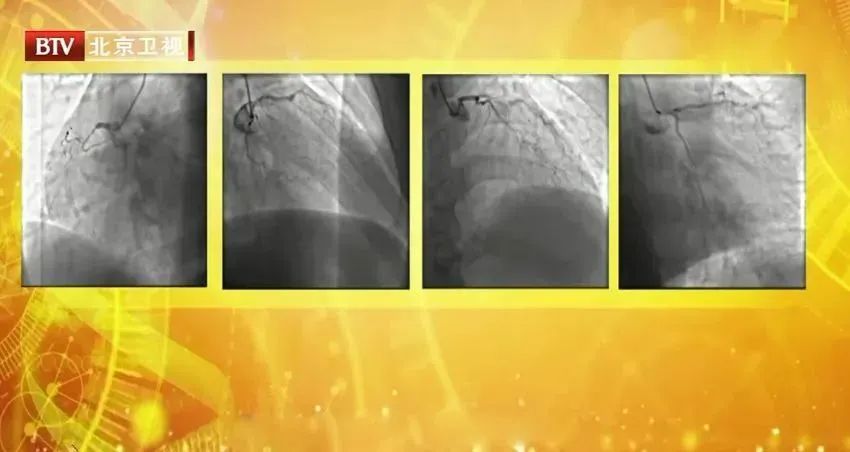

这已经是他,一年前他就已经发生了一次心梗,原因就是遇到了“无声的殺手”,且一直没有好好重视它。

它是动脉粥样硬化,

心梗、中风等多种心血管问题的罪魁祸首!

坏胆固醇会堆积在血管壁上,

使血管变窄,血流受阻,甚至闭塞,

能直接导致动脉粥样硬化的形成,

对血管的损害大。